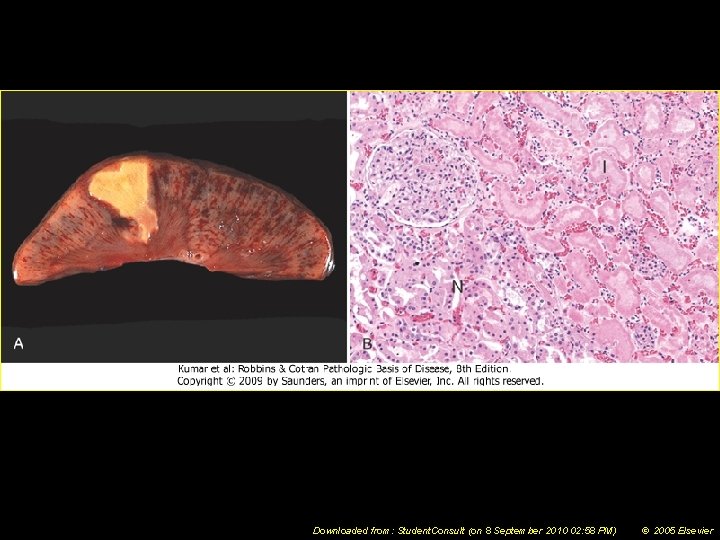

Coagulative Necrosis • Cell’s basic outline is preserved • Homogeneous, glassy eosinophilic appearance due to loss of cytoplasmic RNA (basophilic) and glycogen (granular) • Nucleus may show pyknosis, karyolysis or karyorrhexis

Downloaded from: Student. Consult (on 8 September 2010 02: 58 PM) © 2005 Elsevier

Splenic infarcts -- gross

3 stages of coagulative necrosis (L to R) -- micro